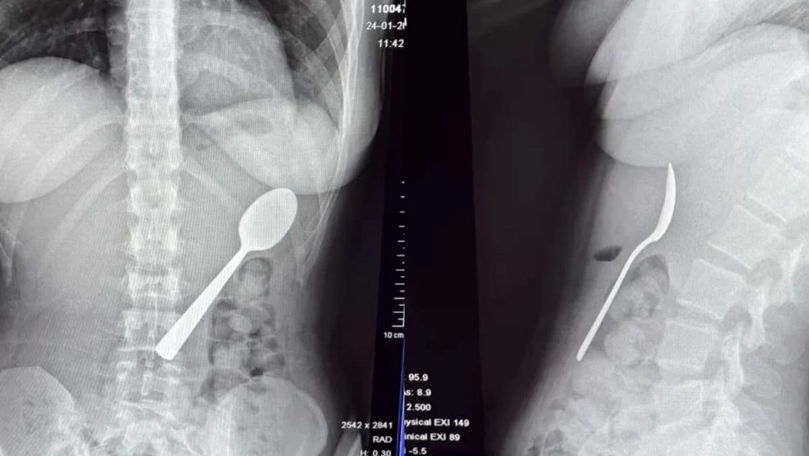

O femeie de 28 de ani din Belgia a trăit momente terifiante după ce a înghițit accidental o lingură de 17 centimetri. Incidentul s-a produs în timp ce mânca iaurt pe canapea, iar totul a pornit de la o reacție neașteptată a câinelui ei, un energic Hungarian Vizsla pe nume Marley.

O tânără din Belgia a înghițit o lingură de 17 cm din cauza câineluiFoto: Jam Press

Medicii au decis să îi îndepărteze lingura sub anestezie locală, evitând o operație deschisă. Procedura a fost delicată, necesitând rotirea lingurii în interiorul stomacului pentru a putea fi extrasă în siguranță.